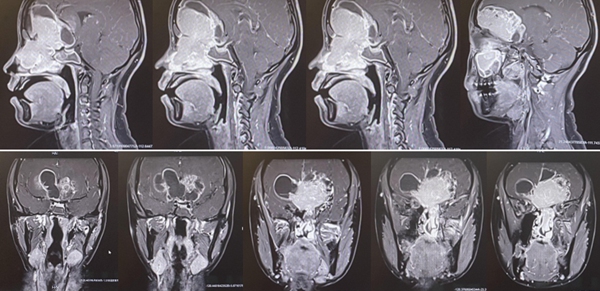

從術(shù)后磁共振和CT檢查看到,腫瘤已經(jīng)被全切,腦組織恢復(fù)很完美,顱底使用鈦板修復(fù)。重慶醫(yī)科大學(xué)附屬第二醫(yī)院供圖

如今,小于已經(jīng)結(jié)束病假,重新回到工作崗位。根據(jù)神經(jīng)外科和耳鼻咽喉科專家的會(huì)診研判,她的顱底愈合和鼻腔黏膜修復(fù)情況都非常良好,可以開始下一步的放化療治療。雖然目前還不能說(shuō)完全治愈了腫瘤,但手術(shù)的成功已為小于開啟了全新的、充滿希望的征程。